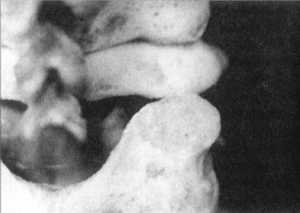

Наклон головы при вправлениях второго суставного отростка также приводит к

переводу сцепившегося вывиха в вывих с высоким стоянием суставных отростков

(рис. 2.12.18, 2.12.19 - вид сзади, сбоку). В позиции сверху определяется прежнее

стояние между отростками (рис. 2.11, позиция "наклон головы вправо",

левый сустав).

Рис. 2.12.18. Наклон головы. Левый сустав.

Вид сбоку |

Рис. 2.12.20. Ротация головы влево. Левый

сустав. Вид сбоку |

Рис. 2.12.19. Наклон головы. Левый сустав.

Вид сзади |

Рис. 2.12.21. Ротация головы влево. Левый

сустав. Вид сзади |